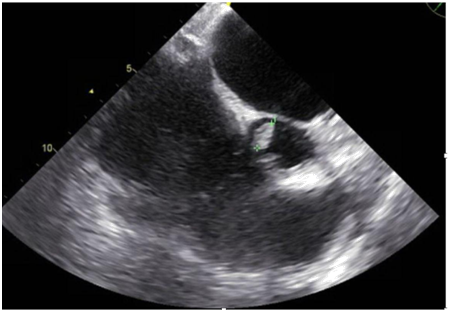

A 47-year-old immunocompetent male with a medical history significant for active intravenous heroin abuse presented to the hospital with fever and respiratory distress. On admission, he was diaphoretic, febrile, and hypoxemic with an oxygen saturation of 70% on ambient air, necessitating intubation and mechanical ventilation. Chest radiography revealed a right lower lobe infiltrate concerning for pneumonia, blood cultures were obtained, and vancomycin and piperacillin-tazobactam were empirically administered. Within 48hours, blood cultures grew Candida tropicalis, and antifungal therapy with micafungin was initiated. Computed tomographic scan of the chest revealed bilateral upper lobe infiltrates and dense consolidations with air bronchograms in the bilateral posterior lobes. Transthoracic echocardiography demonstrated severe aortic thickening and aortic regurgitation but no clear evidence of vegetation despite clinical suspicion for endocarditis. Sites of metastatic infection, including endophthalmitis and septic emboli to the brain were ruled out, and antifungal therapy was adjusted to amphotericin B and flucytosine. A subsequent transesophageal echocardiogram revealed a 1.3cm aortic valve vegetation associated with severe aortic regurgitation, for which he underwent aortic valve replacement with a bioprosthetic pericardial valve. Intra-operative cultures from the aortic valve confirmed Candida Tropicalis. He was discharged to a skilled nursing facility to complete 6weeks of antifungal therapy.

Figure 1 Transesophageal Echocardiogram showing a 1.3 cm vegetation in right coronary cusp.

Figure 2 Transesophageal Echocardiogram showing left atrium dilatation (4.8cm); and severe aortic valve regurgitation.